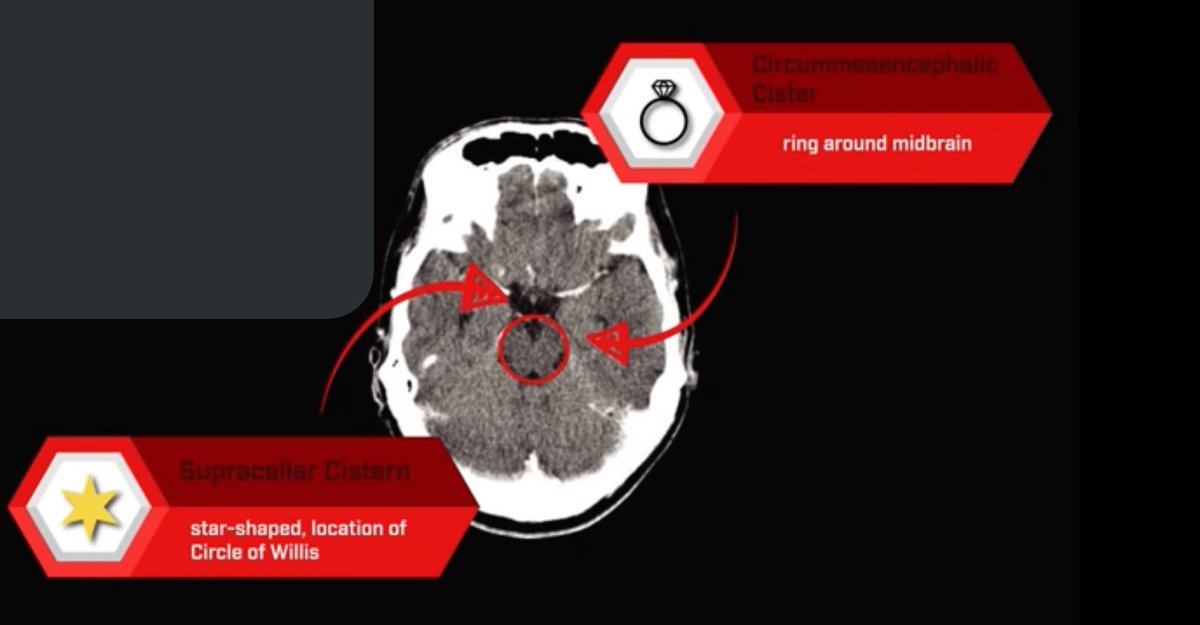

▫️الحرف الثاني هو ال “C”

⬅️ويقصد فيه⬅️ Cisterns

✳️تمثل مساحات مليئة بالسائل الدماغي الشوكي "CSF” وكونها متصلة يعتبر شيء أساسي لل CSF circulation

✳️Related pathology✳️

Mass effect and ⬆️ ICP ➡️ effacing one or more of the cisterns

Subarachnoid hemorrhage

arachnoid cyst